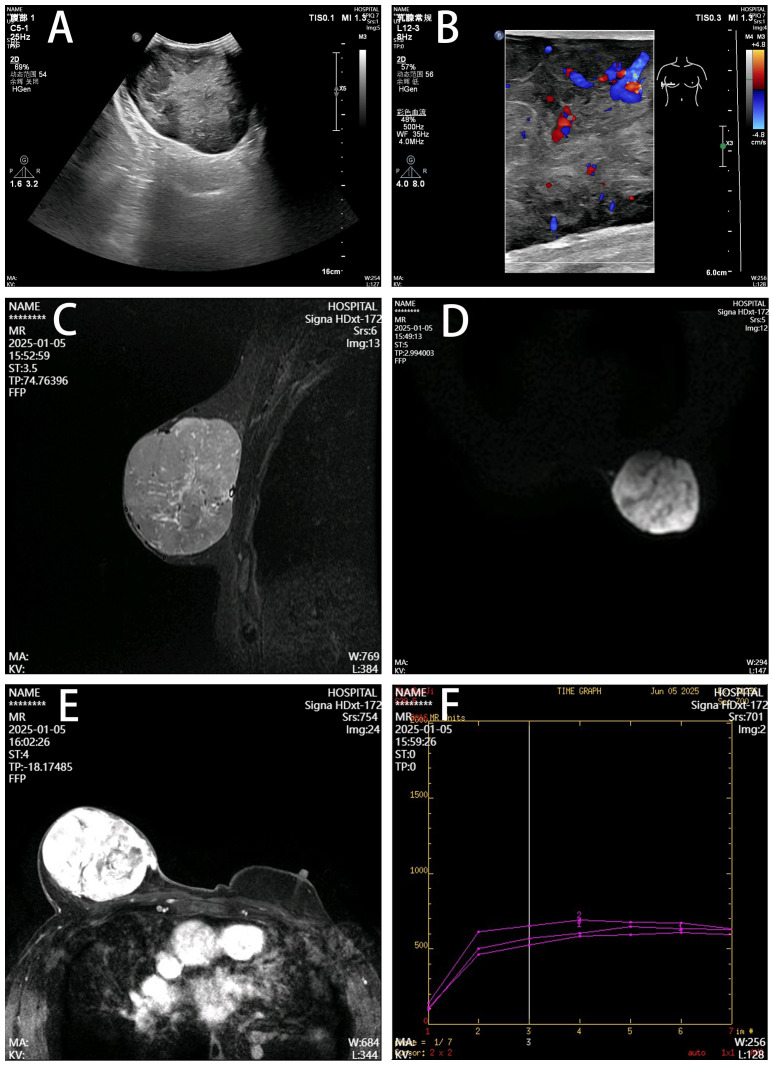

摘要原发性乳房平滑肌肉瘤是一种极为罕见的恶性肿瘤,起源于间质组织。全球报告的男性病例不到10例。本文报告一位84岁男性患者。这是目前文献中最早报道的病例。右乳房有一个无痛的、缓慢增大的肿块。这次弥撒已有10年的历史。这与以往文献记载的典型的快速进展模式形成鲜明对比。临床检查发现右乳房有一个12厘米× 10厘米的可移动肿块。未发现淋巴结病变。超声示低回声病变,BI-RADS 4a级。磁共振成像显示高原型增强。患者接受了单纯性乳房切除术。未行腋窝淋巴结清扫。术后病理及免疫组化证实为乳腺平滑肌肉瘤。患者谢绝辅助放疗。术后6个月随访,未见局部复发和转移。这个病例向临床医生说明了几点。免疫组化是诊断乳腺梭形细胞瘤的基础。R0手术切除是实现治愈的核心途径。辅助治疗的决定需要充分考虑宿主年龄和肿瘤生物学行为。老年患者衰老微环境可能抑制肿瘤侵袭性进展。

Primary breast leiomyosarcoma is an extremely rare malignancy originating from mesenchymal tissue. Fewer than 10 male cases have been reported globally. This paper reports an 84-year-old male patient. This represents the oldest reported case in the current literature. A painless, slowly enlarging mass was present in his right breast. The mass had a 10-year history. This contrasts sharply with the typically rapidly progressive pattern documented in previous literature. Clinical examination revealed a mobile mass measuring 12 cm × 10 cm in the right breast. No lymphadenopathy was detected. Ultrasound showed a hypoechoic lesion classified as BI-RADS 4a. Magnetic resonance imaging demonstrated plateau-type enhancement. The patient underwent simple mastectomy. Axillary lymph node dissection was not performed. Postoperative pathology and immunohistochemistry confirmed the diagnosis of breast leiomyosarcoma. The patient declined adjuvant radiotherapy. Follow-up at 6 months postoperatively showed no local recurrence or metastasis. This case indicates several points to clinicians. Immunohistochemistry serves as the cornerstone for diagnosing spindle cell tumors of the breast. R0 surgical resection constitutes the core approach for achieving cure. Decisions regarding adjuvant therapy require full consideration of host age and tumor biological behavior. The senescent microenvironment in elderly patients may suppress aggressive tumor progression.